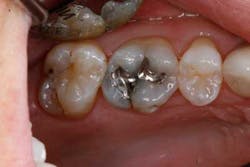

An example of an ideal case for which bulk filled composite (i.e., Tetric EvoCeram® Bulk Fill) is indicated is a 43-year-old female who presented with a defective amalgam restoration on the occlusal of tooth No. 14 (Figs. 1 and 2). The treatment plan involved removing the defective amalgam restoration, any secondary caries, and restoring the tooth with a direct bulk-fill composite (i.e., Tetric EvoCeram® Bulk Fill).